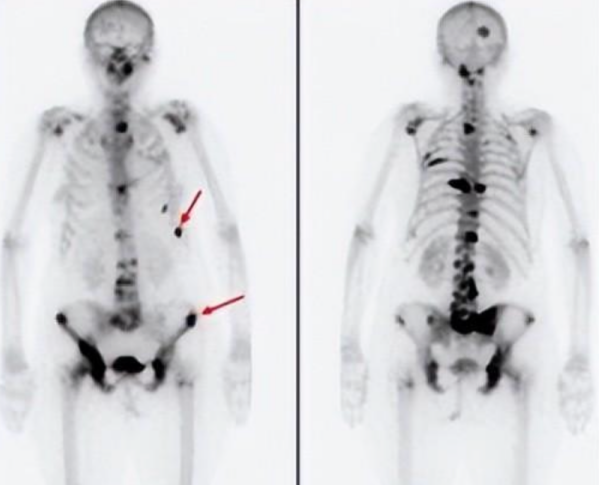

临床应用-肿瘤多发骨转移

如图所示,黑点表示病变部位, 骨扫描发现了全身多处病变,为临床诊治提供大量信息,有下列适应症:

(1)帮助确定原发骨肿瘤的范围、转移病灶以及检测疗效;